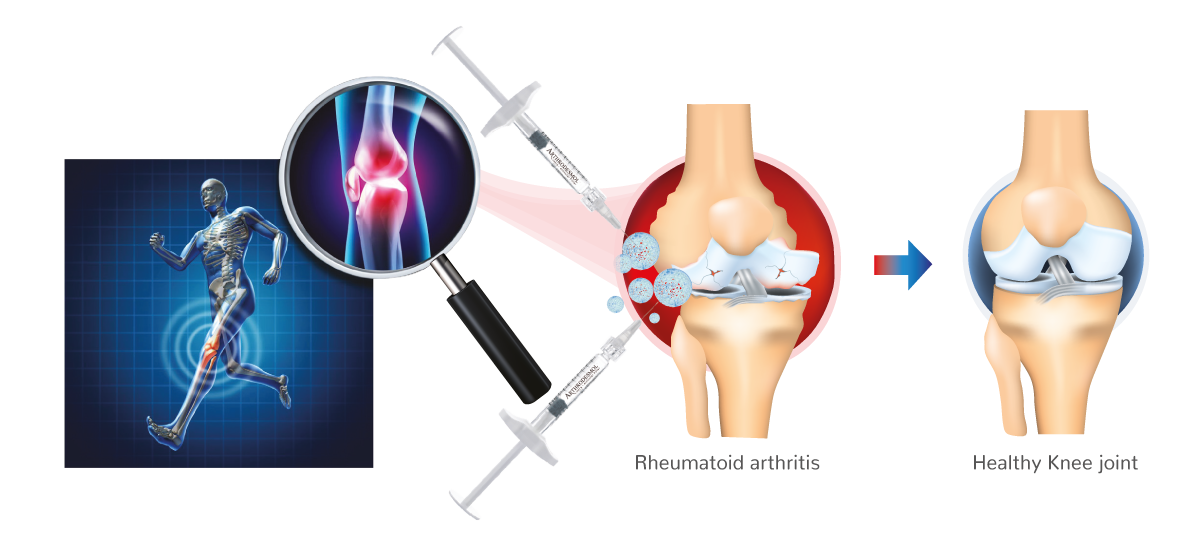

intra articular filler

Often, the arthritis including the rheumatoid starts with the inflammation in synovial membrane of the joint.

Unique HA* with a Specific Extracellular Peptides

Mimics Matrix for a reponse of OA

Biomimetic Matrix Peptides Specific in OA

- Stopping the cartilage degradation and joint degeneration.

- Decrease the synovial inflammation – pain relief.

- Peptides used to block cytokines – Anti-inflammatory and pain relief.

- Peptides improve the pain control, because of the different action mechanisms in the knee joint.

- Clinical studies demonstrate the efficacy regarding the decreasing of pain after one week vs convectional treatment witch showed an improvement after 3 months. (1)

Benefits of Peptides in OA